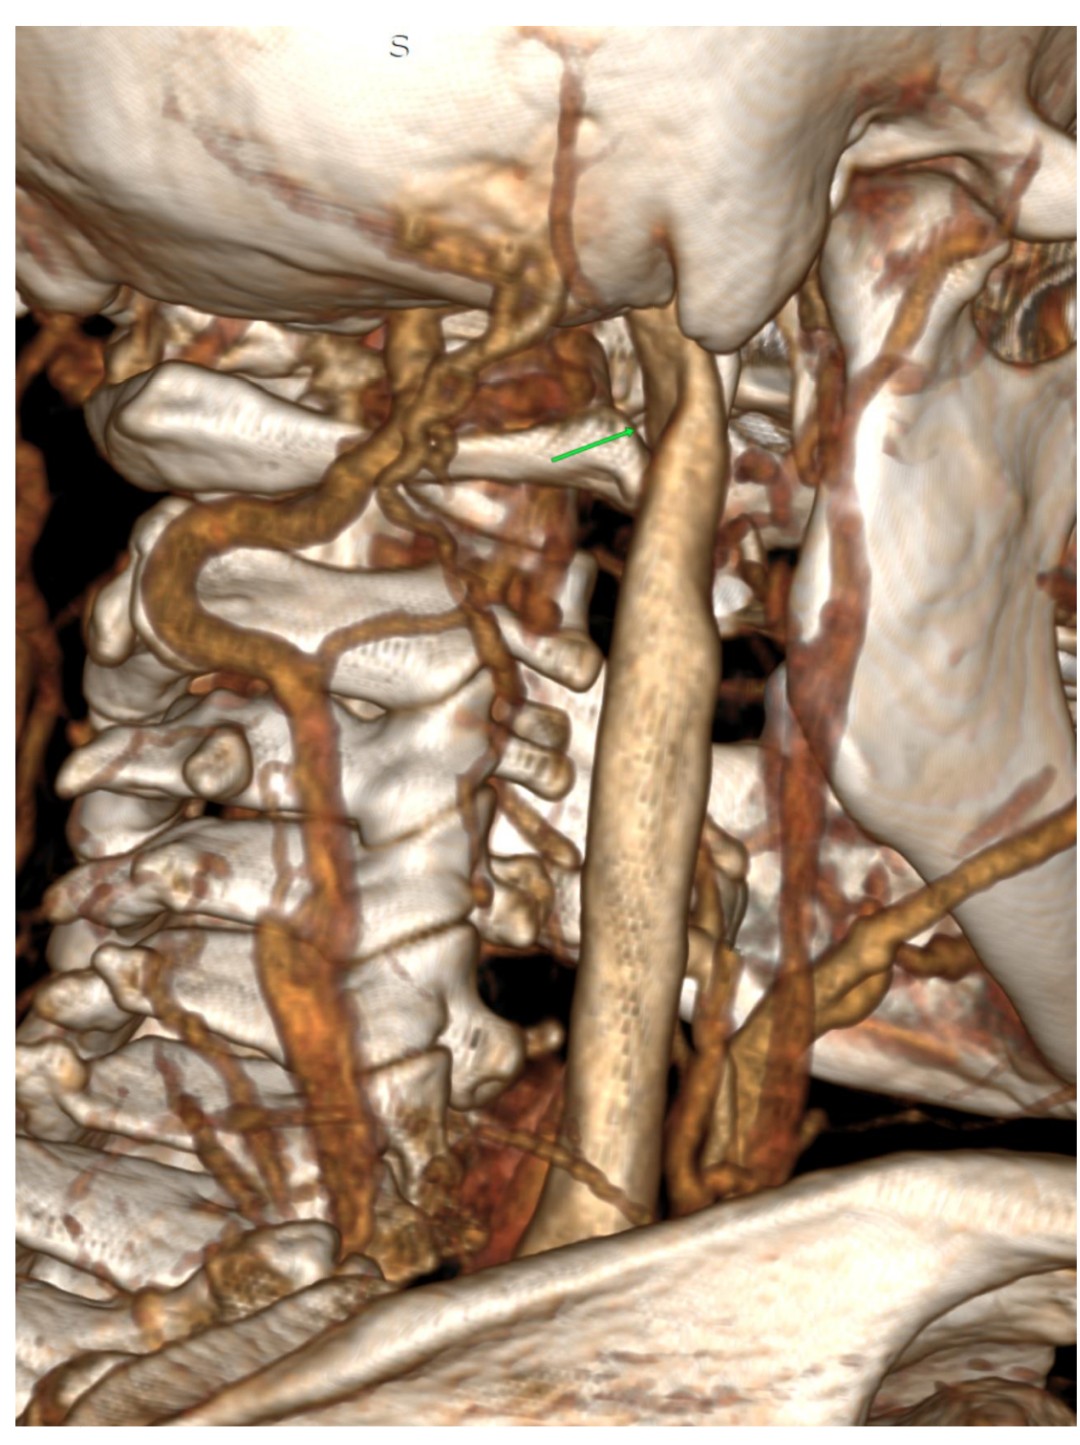

I have edited my post one more time, it must be my anxiety. I have added a picture of my scan with contrast. My elongated styloid processes are trapping my jugular vein. My carotid artery is off track… :scream:

@Hamela - Your styloids aren’t terribly long, but they are exceedingly thick, especially the left one which is a bit more angled than the right one. The right one is more curved. The thickness & angles of growth can significantly play into the symptoms & compression the styloids are causing.

I don’t know how significant it is that your right internal carotid artery is out of place even though Dr. Middleton made note of it, unless you’re also having symptoms related to your carotid artery which would be facial numbness, eye pain, neck pain, temporary visual loss or partial visual loss in one eye, dizziness, & headaches (these may differ somewhat from those caused by IJV compression). TIAs (mini strokes) are often also a symptom pointing to compression or irritation of the carotid artery(ies). It is possible your body has simply adapted to its new location w/o any problem.